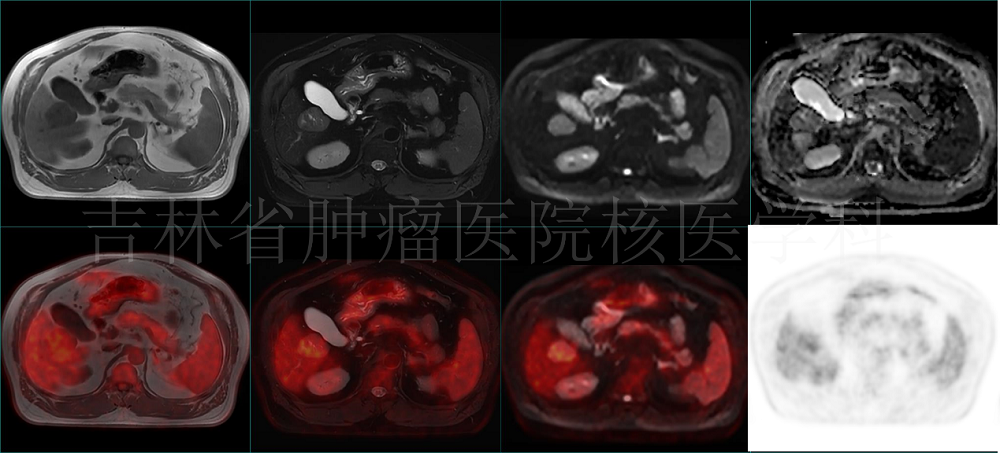

病例1 PET/MR 肝占位定性:肝右葉占位,T1WI呈低信號,T2壓脂呈混雜高信號,DWI呈高信號,ADC值減低,伴糖代謝增高,提示惡性(病理結(jié)果:HCC)